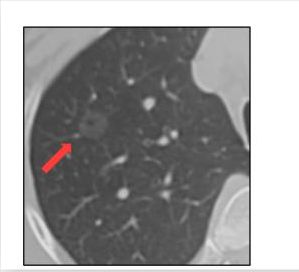

磨玻璃结节

结节长相:肺内密度轻微增加,增加程度小于实性改变,呈模糊的云雾状,并可见其内血管和支气管纹理。

产生原因:根据肺部磨玻璃影内部成分均一程度的不同,磨玻璃结节又可分为单纯磨玻璃结节及混合型磨玻璃结节。造成磨玻璃结节的原因包括感染性病变、肿瘤等多方面。

一旦体检报告出现“磨玻璃结节”,请不要着急“一刀切”。70%磨玻璃结节发展很慢,无须急忙手术“一刀切”,更不是切的越多越好,随访是“上上策”。

我们研究发现,磨玻璃结节型的肺腺癌预后很好,5年总体生存率达98.99%,明显高于整个肺腺癌人群的总体生存率。

这个结果给了我们思考,虽然有些磨玻璃结节患者已经是浸润性腺癌(即已进展到浸润后状态),但这部分患者经过合理有效的手术治疗后,同样能够获得理想的远期生存。

所以我们认为“磨玻璃结节”型肺癌是一种“懒癌”,长期随访跟踪,适当时间手术不会影响患者的治疗效果和生存率。